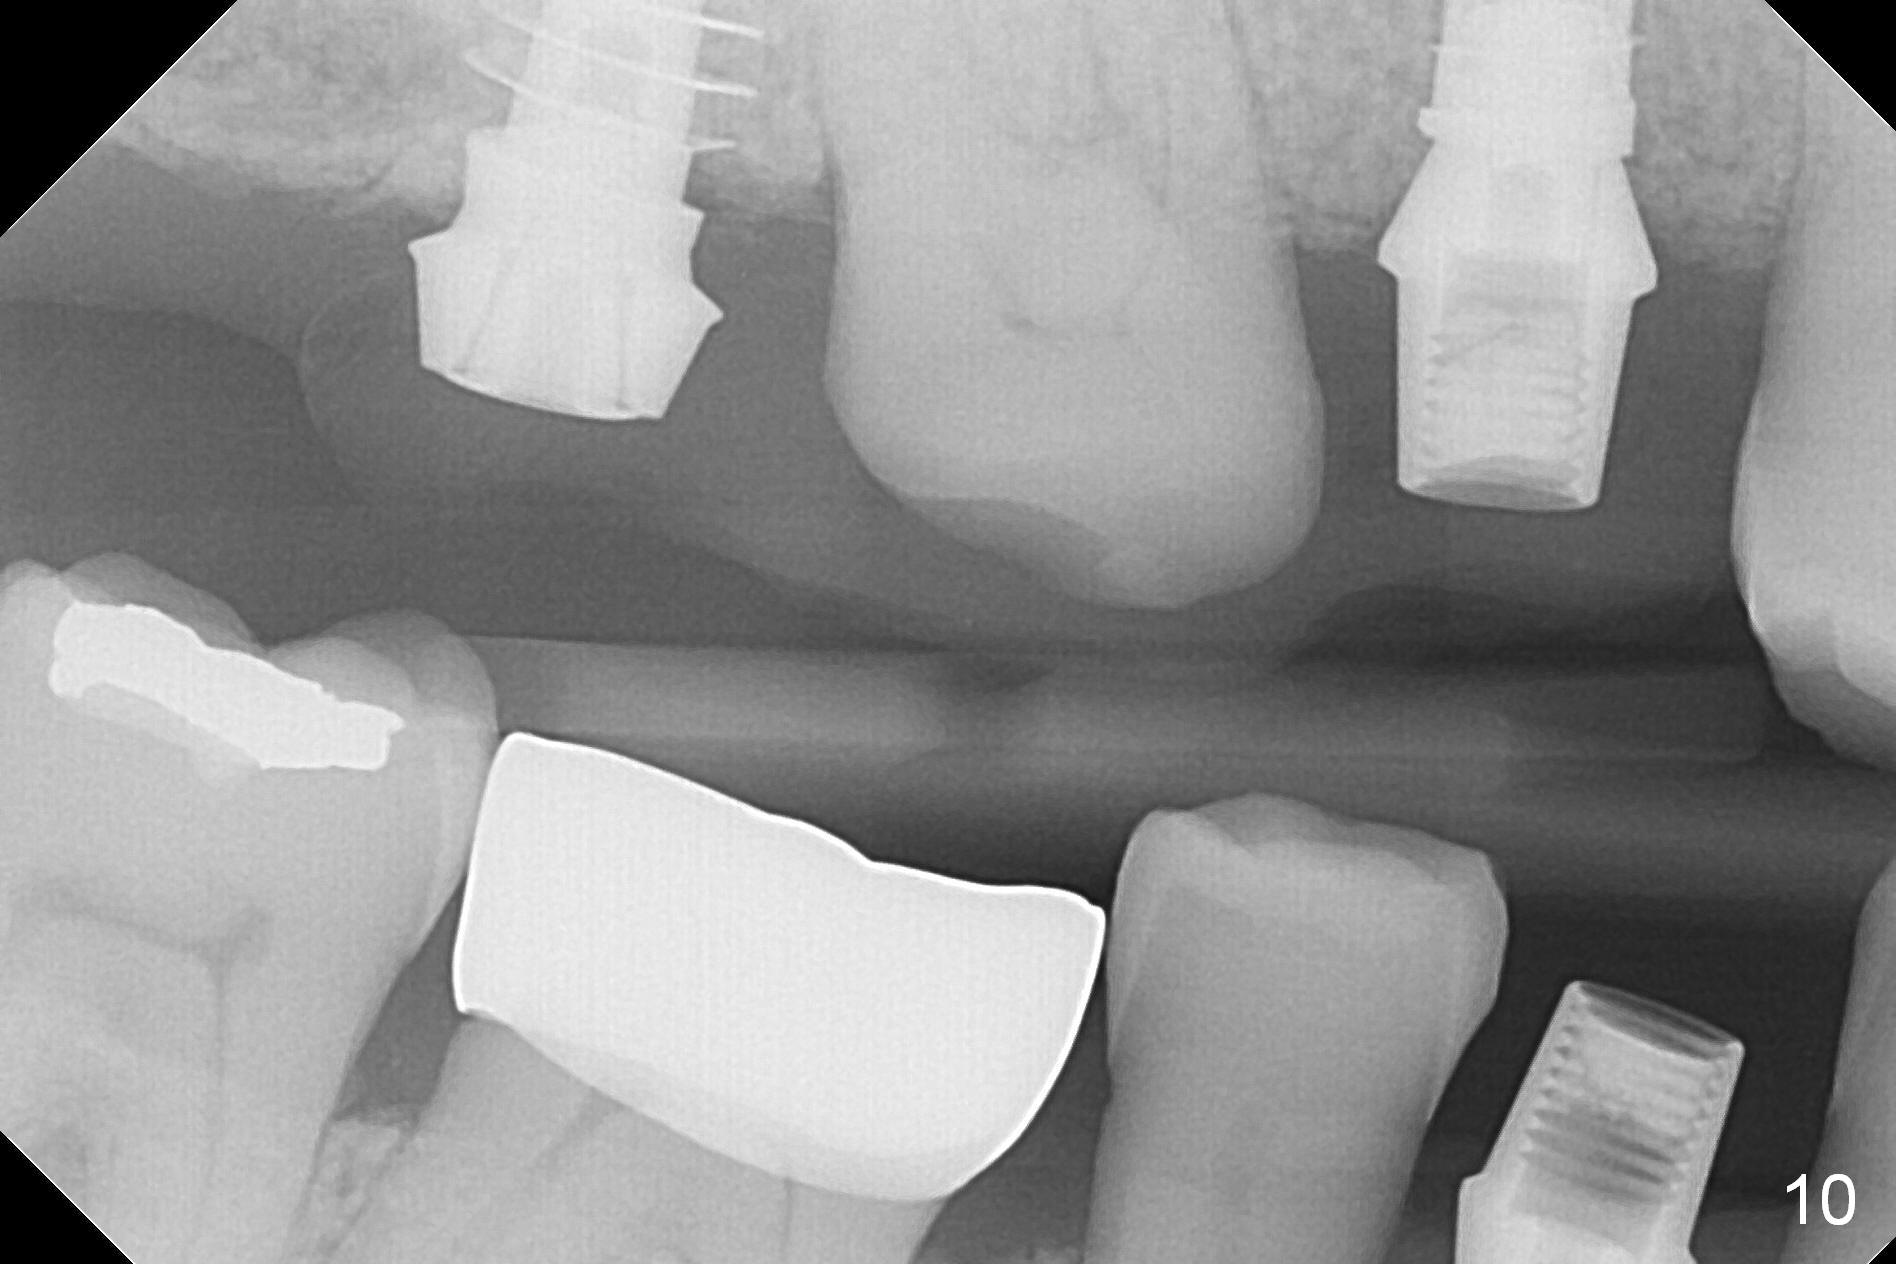

In fact the upper provisional has been extended to cover #2-4 three months postop. When the patient returns again, it is approximately 4 months postop for #2 and 4 (Fig.9,10) and 3 months for #28. Reline or make the provisional so that the teeth #5 and 29 will be intruded (Fig.11 preop pan for comparision). The tooth #30 appears to have been intruded for the past 4 months. The provisional at #3 is short so that the tooth #30 may be able to erupt (Fig.12).